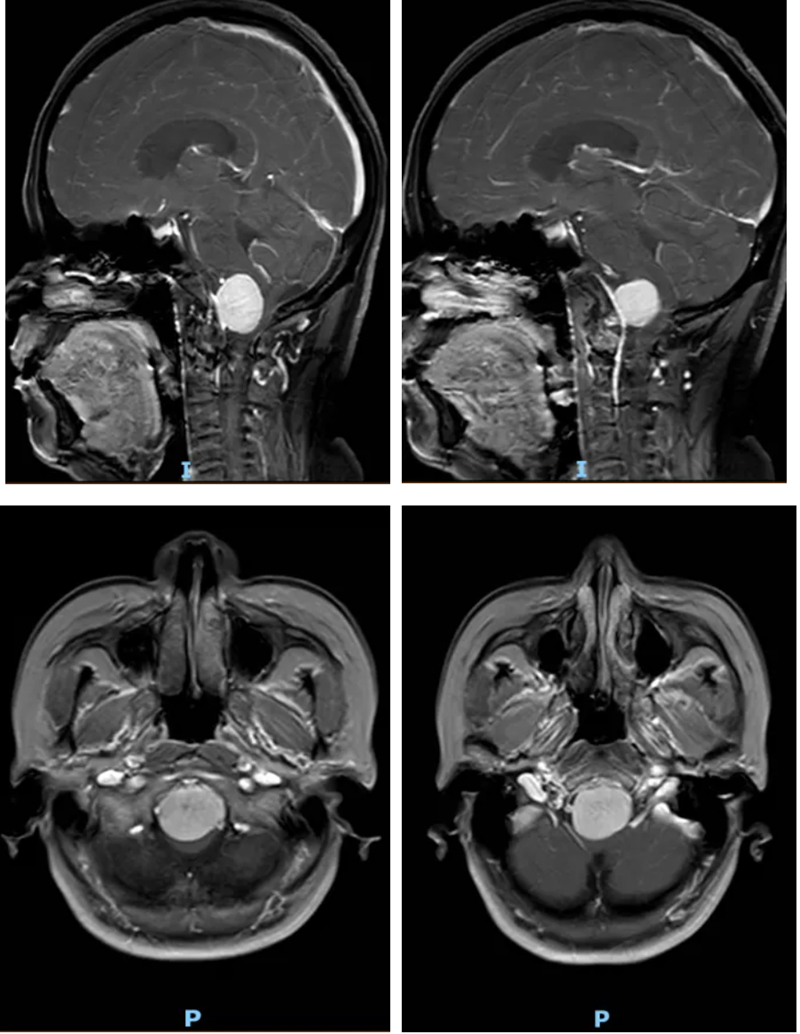

進一步檢查后,金陽醫院神經外科三病區團隊明確了李女士的病情。李女士的腫瘤生長位置極為特殊,位于枕骨大孔區。這一區域是大腦與脊髓連接的關鍵通道,被稱為神經外科手術的“生命禁區”,腫瘤恰好位于延髓前方。而延髓作為控制心跳、呼吸、血壓的“生命中樞”,其周邊解剖結構復雜,緊鄰椎動脈和后組顱神經,手術空間異常狹小,操作難度堪稱神經外科領域的技術高峰。

術后復查頭顱CT和MRI結果顯示,李女士腦部的腫瘤被徹底切除,延髓所受壓迫完全解除。術后恢復期間,在神經外科、麻醉科(手術室)、電生理監測團隊、神經重癥及術后護理團隊的多學科協同照料下,李女士恢復順利。她的頭昏、頭痛癥狀徹底消失,肢體肌力明顯改善,未出現任何新發神經功能障礙,目前已逐步恢復正常生活能力。